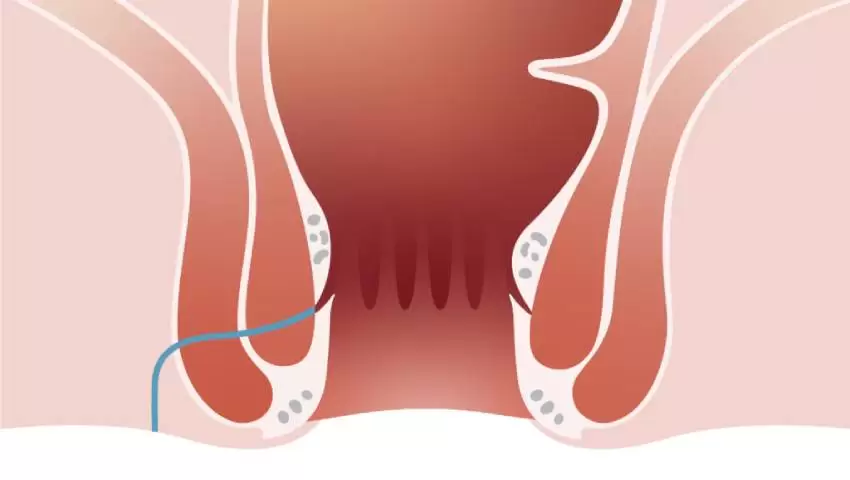

VAAFT (Video-Assisted Anal Fistula Treatment) is a modern, minimally invasive technique used to treat anal fistulas ...

What is VAAFT and How Does It Treat Fistula-in-Ano?

Have you undergone surgery for an anal ..